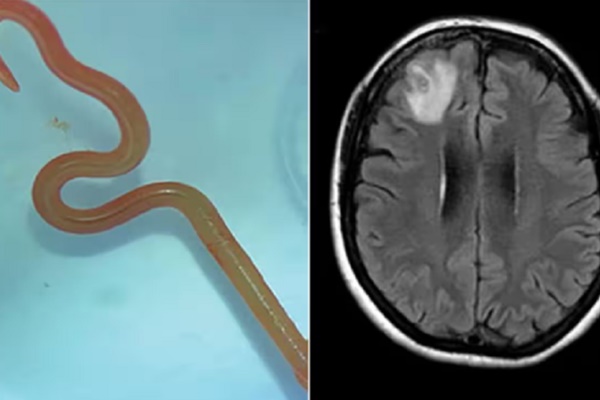

Cận cảnh con giun và vùng não thể hiện tình trạng bất thường ở bệnh nhân.

Sau khi phân tích, họ xác định đây là một con giun đũa có tên khoa học Ophidascaris robertsi. Đội ngũ y bác sĩ của Bệnh viện Canberra cho rằng đây là trường hợp đầu tiên trên thế giới phát hiện giun đũa trong não người.

Con giun lấy ra từ não bệnh nhân.

Loài giun đũa này thường ký sinh ở trăn thảm, cụ thể là ở thực quản và dạ dày của vật chủ trước khi trứng giun thải theo đường tiêu hóa.